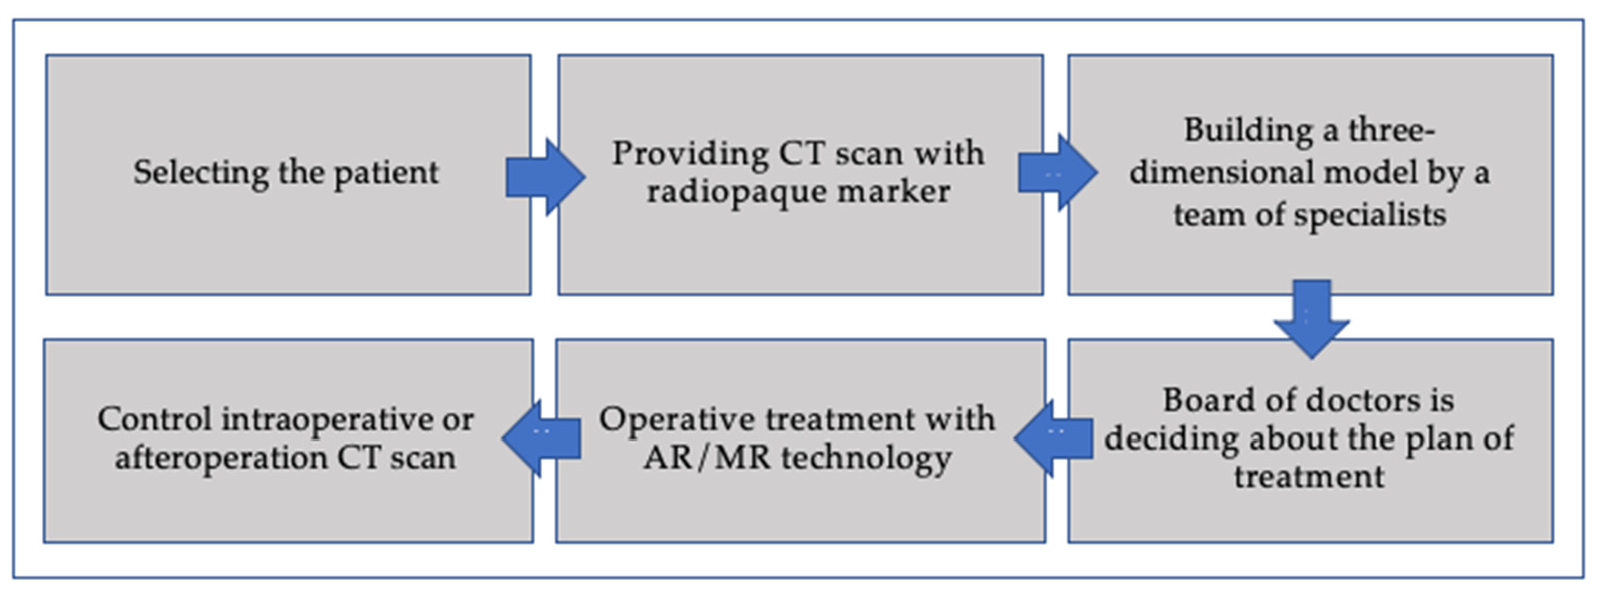

- Algorithm for the application of augmented reality in surgery